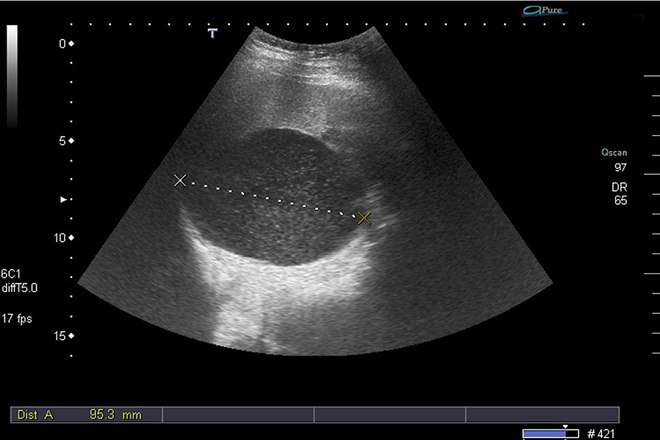

El diagnostico se hace con base en la historia del paciente, el examen físico y los hallazgos en los estudios  de imagen. Los  estudios diagnósticos de elección son el  USG  y la TC abdominal, los  cuales proporcionan información sobre la morfología, composición, localización y relación con órganos vecinos.